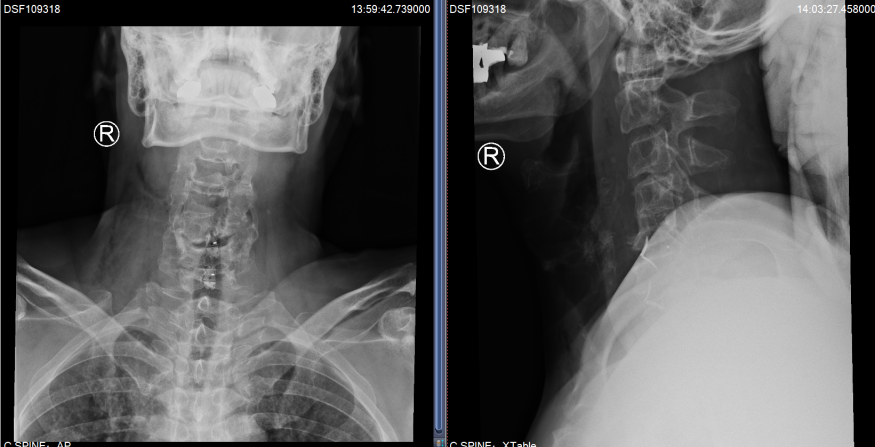

C5/6、C6/7椎间盘突出明显,椎管狭窄,脊髓受压严重

就这样,2022年3月,Hester办理了住院手续,在进一步的详细评估后,姜主任制定了经前路减压融合术的手术方案。与后路椎管扩大成型术相比较,具有创伤小、直接减压与恢复快的优点。但由于Hester颈椎的先天畸形与严重的骨质增生,手术难度却增加了很多。手术当天,在麻醉科医生黎鹏与手术室护士的密切配合下,姜为民主任带领王喜安副主任和赵星毅博士,经过两个多小时的精雕细琢,将增生的骨赘在狭窄变形的椎间隙里一一切除,解放了受压的脊髓,完成了这台特殊的“颈椎前路椎间盘切除+椎间融合术”。Hester在术后第一天就激动地告诉姜主任:“Right after the surgery I found the balance problem was gone. I can stand again on one leg without crashing on the floor now and the numbness in the finger is reduced.”(我右手持续了3年之久的麻木感已经明显缓解,佩戴颈托后试着下床行走,发现术前那种失去平衡的症状不见了,甚至单足站立也不怕摔倒)。

术后复查X片,C5/6和C6/7椎间隙高度恢复满意